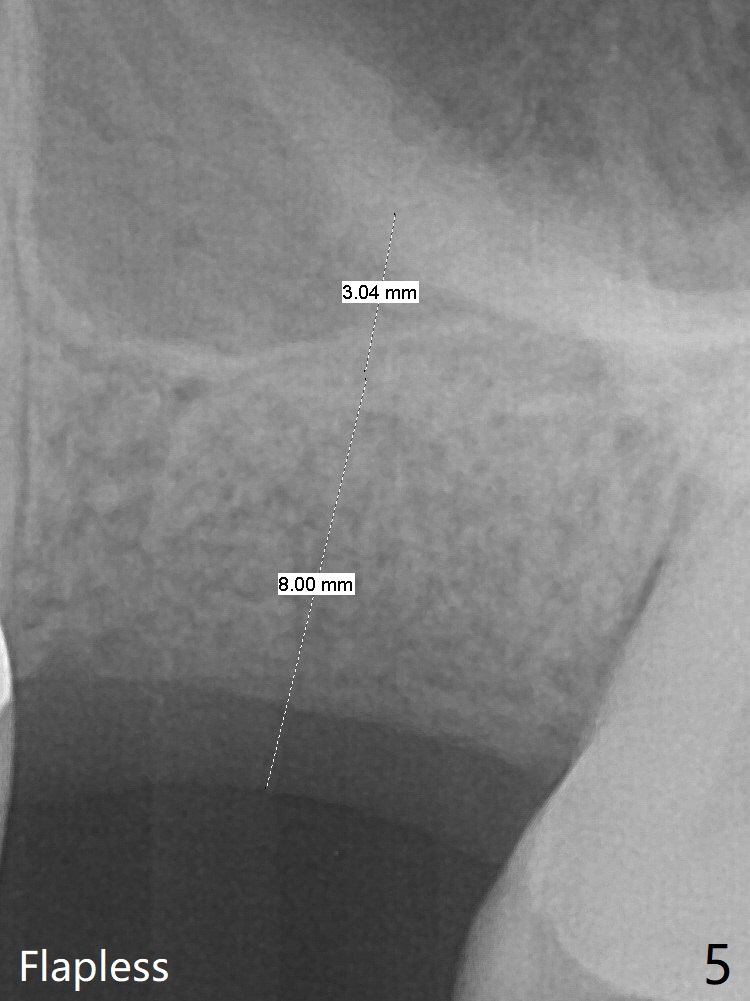

A 61-year-old woman has pain after RCT at #14 (Fig.1). Exam shows subgingival crack. After difficult extraction, allograft with Osteogen is placed in the 3 sockets, followed by Osteogen plug and 4-0 Chromic Gut Suture. The distal gingiva appears to be migrating into the center of the sockets (Fig.2 arrow). Due to insurance issue, an implant will be placed early next year. The patient returns 9 months post extraction (Fig.3). If the ridge proves to be not so wide, make incision, start osteotomy with 1.6 mm pilot drill, followed by 4.3 mm Magic Drill for 7 mm and 3.8 mm Magic Expander for another 2 mm (sinus lift, BEB, Fig.4). Otherwise start Magic Split. If the bone is dense, use drills and Expander as mentioned above with the depths 2 mm more (Fig.5), followed by Magicore. The tissue-level implant improves the crown/implant ratio over the FC. After socket healing, gingival cuff height is stable. The cuff of Magicore is easy to determine vs. immediate case.